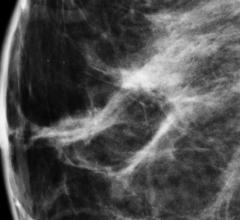

Breast density, or fibroglandular density, is found through breast imaging and compares the amount of fat to the amount of tissue.

Dense breast tissue can mask the appearance of tumors and limit the performance of mammography. When used as an adjunct ...

Since the implementation of routine screening mammography, we have seen a 30 percent reduction in breast cancer ...

The last 20 years have brought about great advances in breast cancer detection and treatment. Among them has been the ...